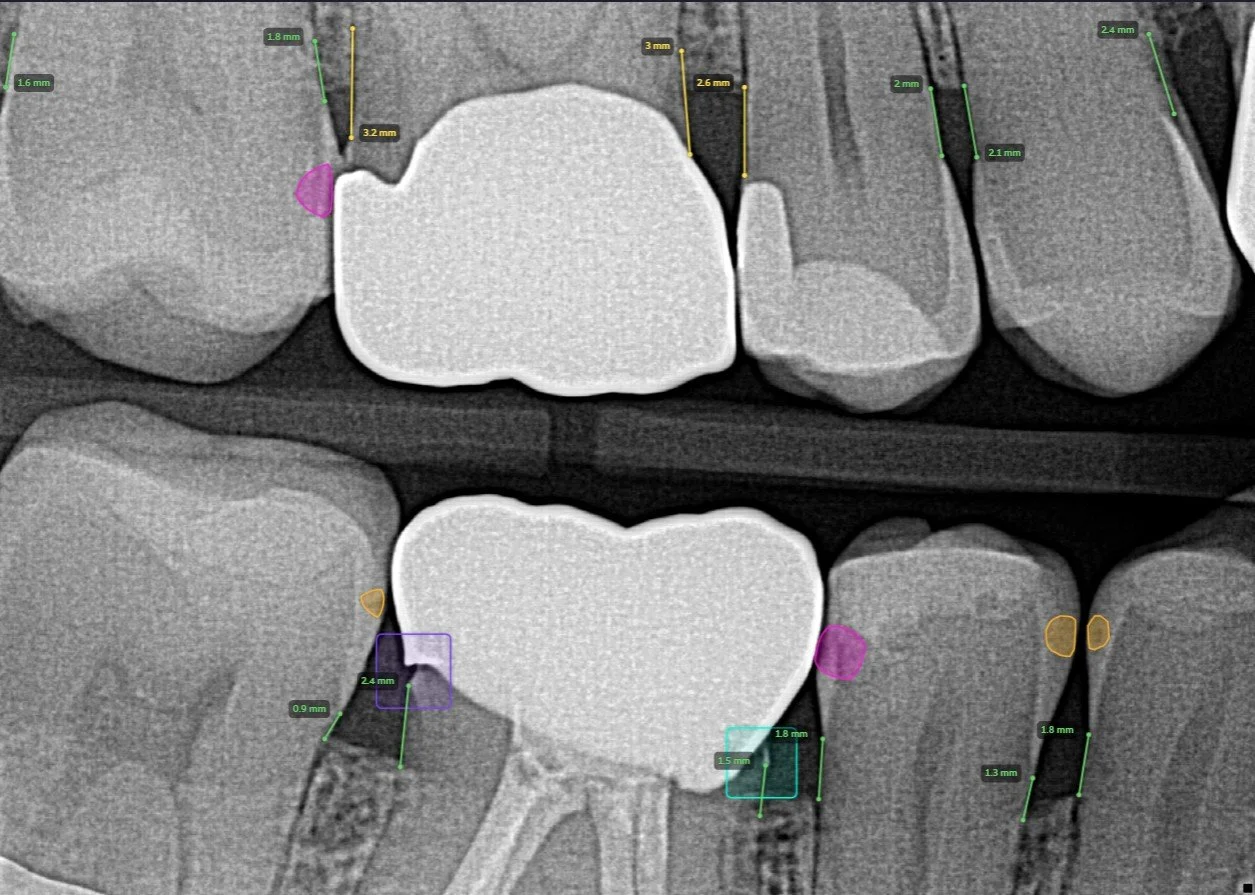

DIGITAL X-RAYS AND PEARL A.I. RADIOGRAPHIC INTERPRETATION

We utilize digital dental radiographic technology which reduces exposure to radiation significantly from using film. Aside from the largely reduced exposure time, the results of the image appear within seconds reduce the need of toxic developing solutions which are harmful to the environment. We also supplement our diagnosis and interpretation of our X-Rays by utilizing Pearl Artificial Intelligence which can read dental radiographs with accuracy of 96% according to a study by the prestigious UCLA School of Dentistry